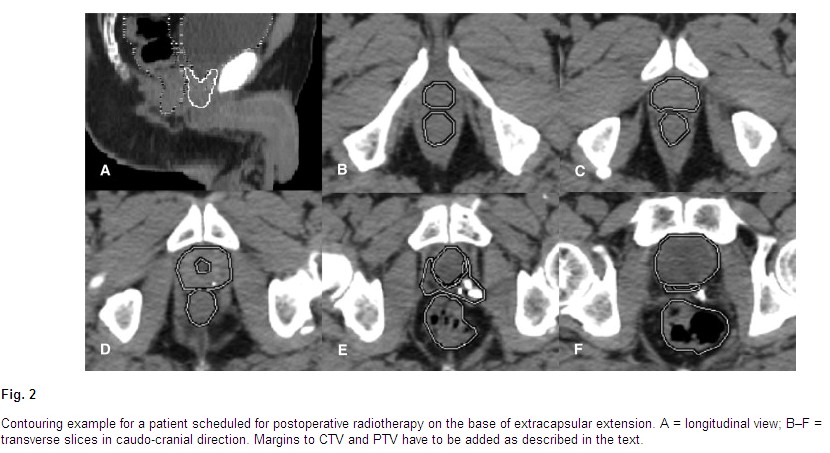

NCCN guidelines. A Typical technique from RTOG P-0011 which compares postOP radiation

alone (63 - 66Gy) with radiation plus two years of Lupron, the radiation ports are

shown here and here and here. The RTOG has

a contouring site

here, other images for contouring: